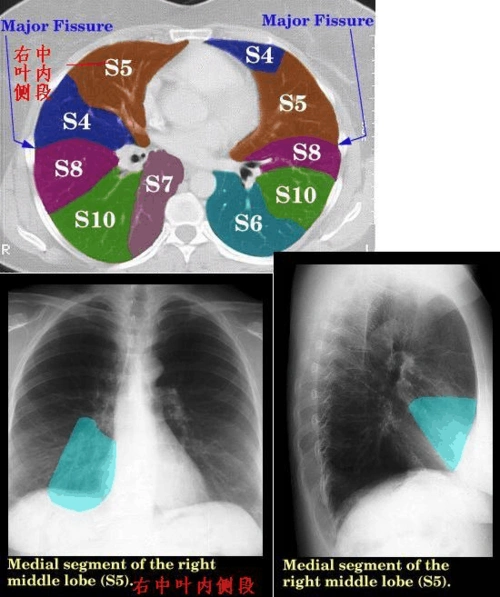

看胸部影像:不一样的肺分段

影像学肺叶分段